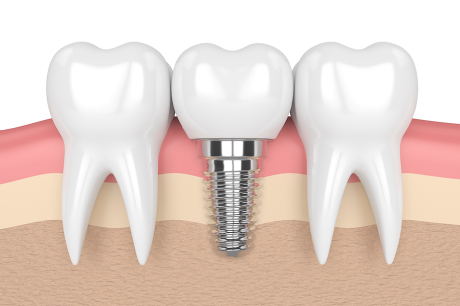

診療メニュー

当診療所では、患者さん一人ひとりの症状に合った以下の治療方法で、お口の健康を守っていきます。